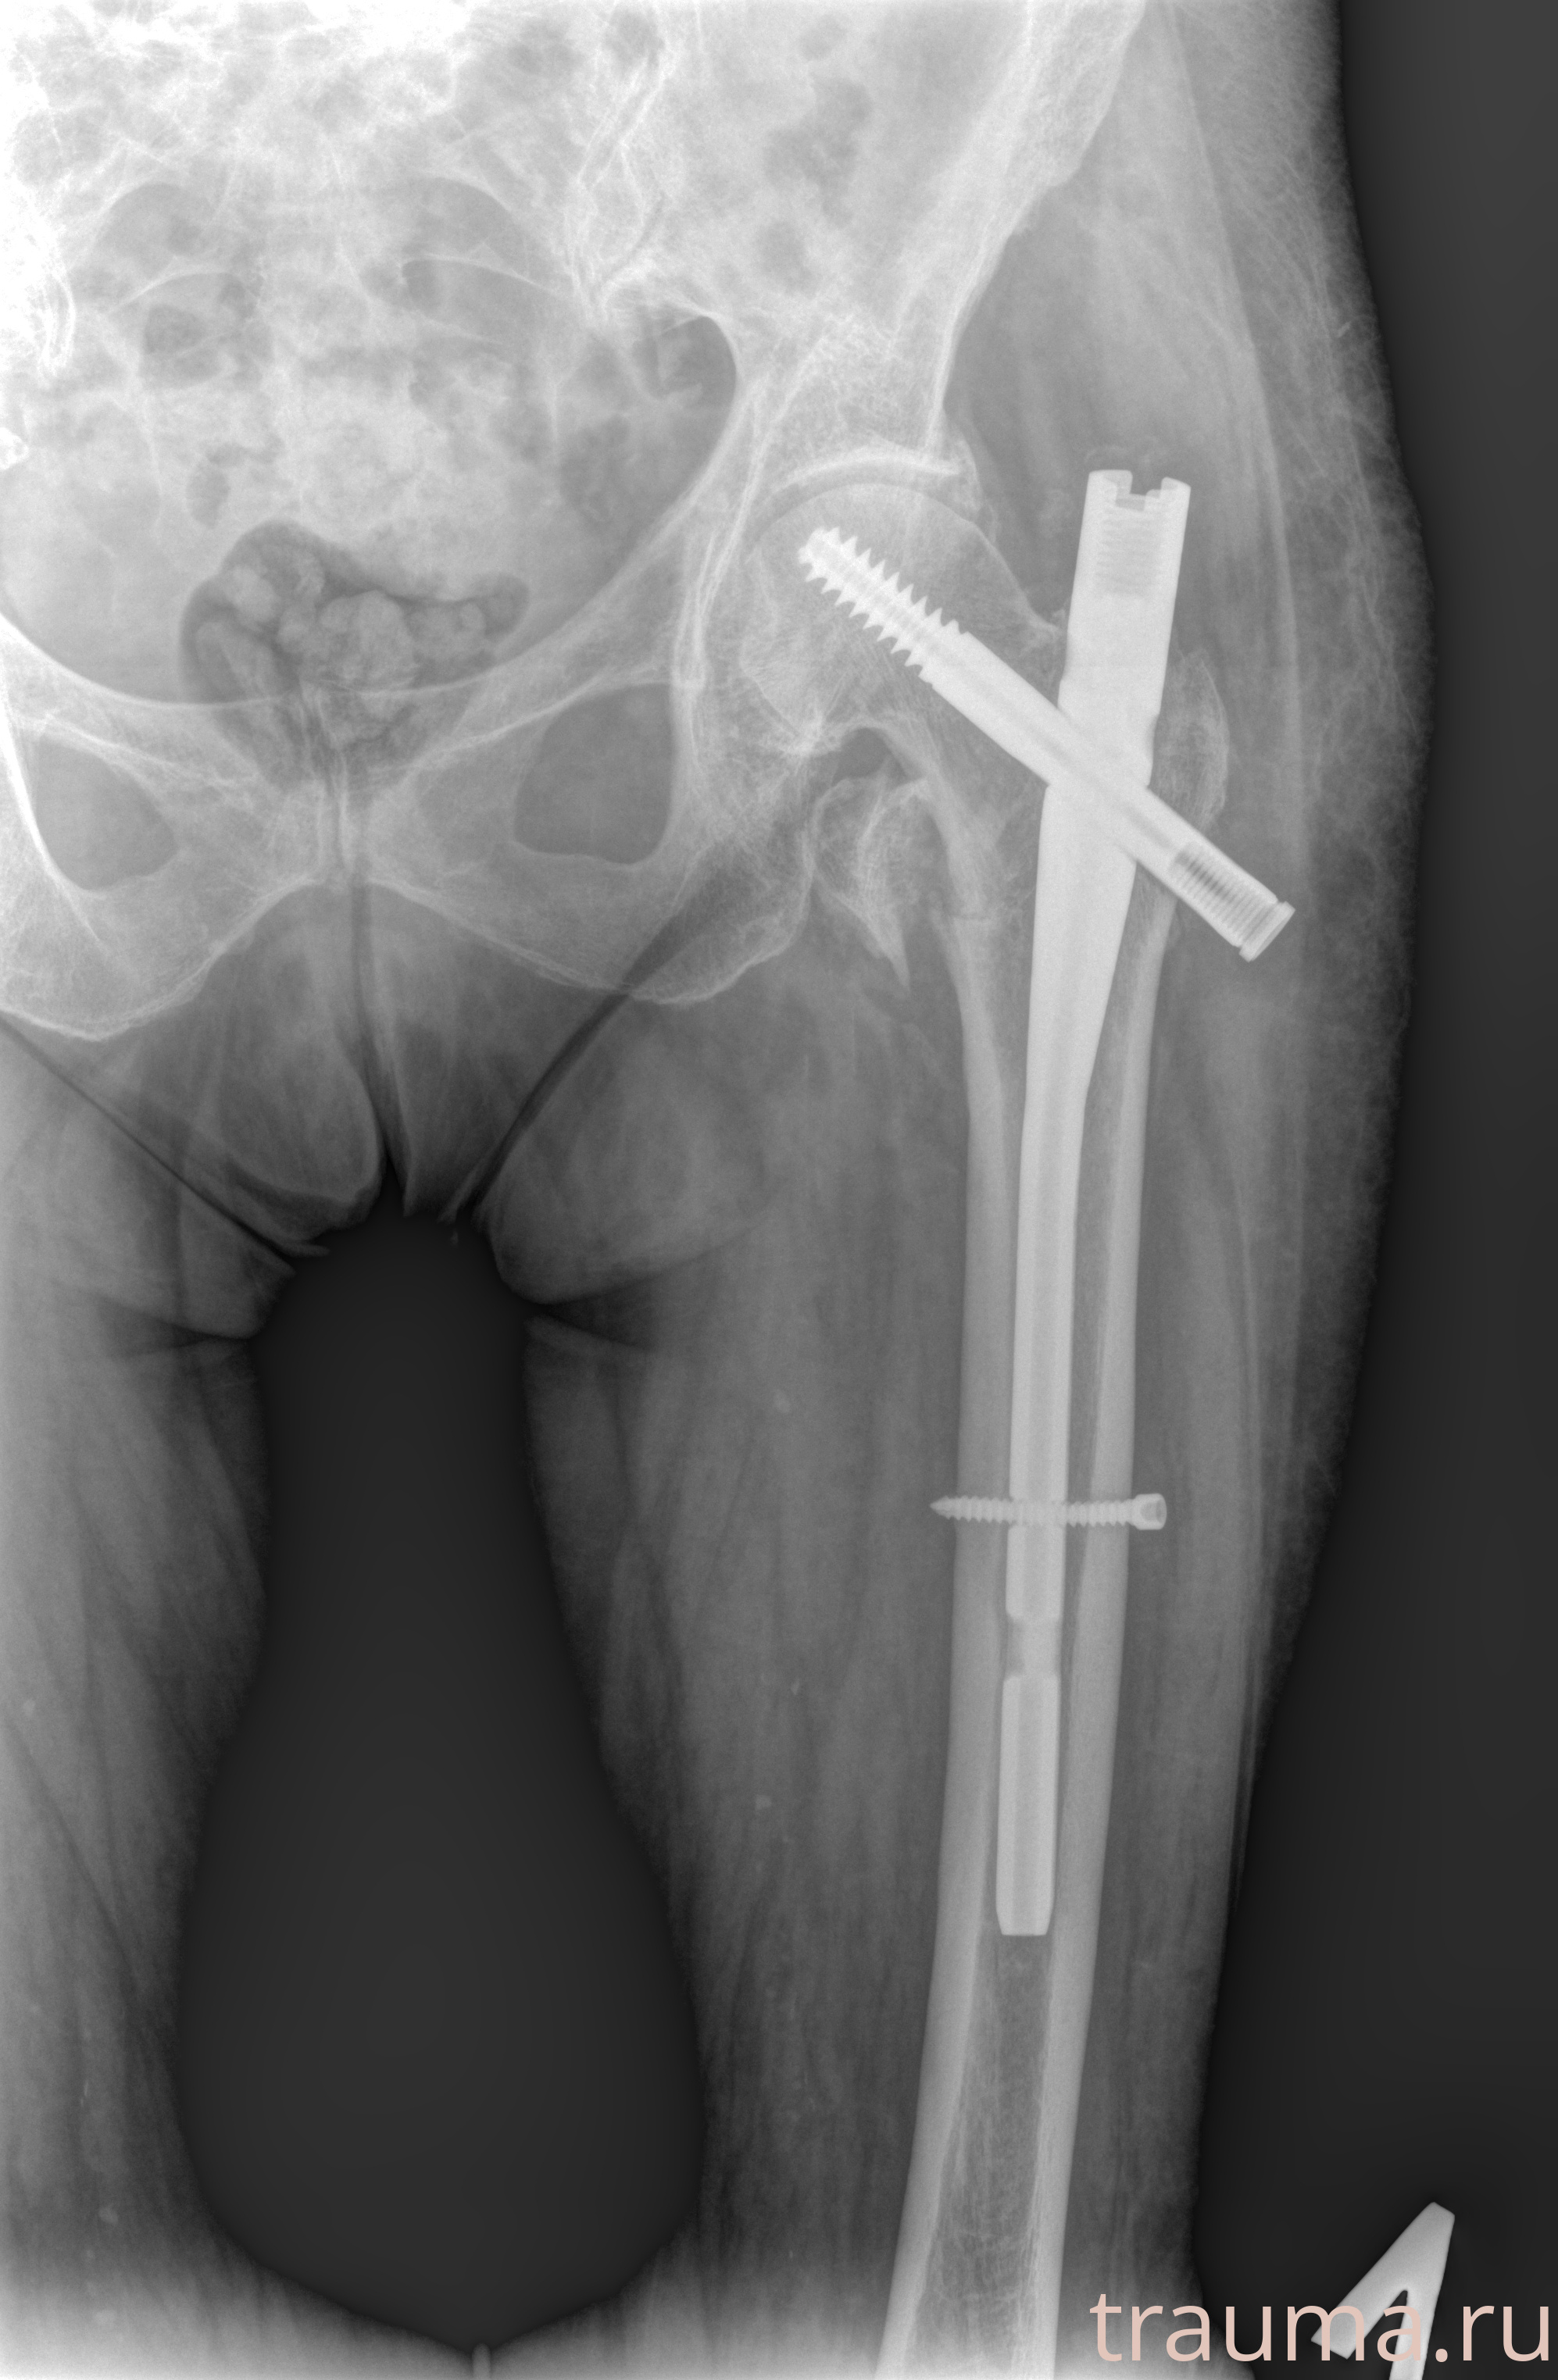

Рентгенограммы

Рентген на дому: по вашему адресу приезжает врач-рентгенолог, травматолог-ортопед с мобильным рентгеновским аппаратом, проводит диагностику травмы или заболевания, делает необходимые рентгенограммы, дает рекомендации по дальнейшему лечению. Получить качественные снимки в домашних условиях возможно благодаря уникальной методике, разработанной МосРентген Центром для института  Склифосовского